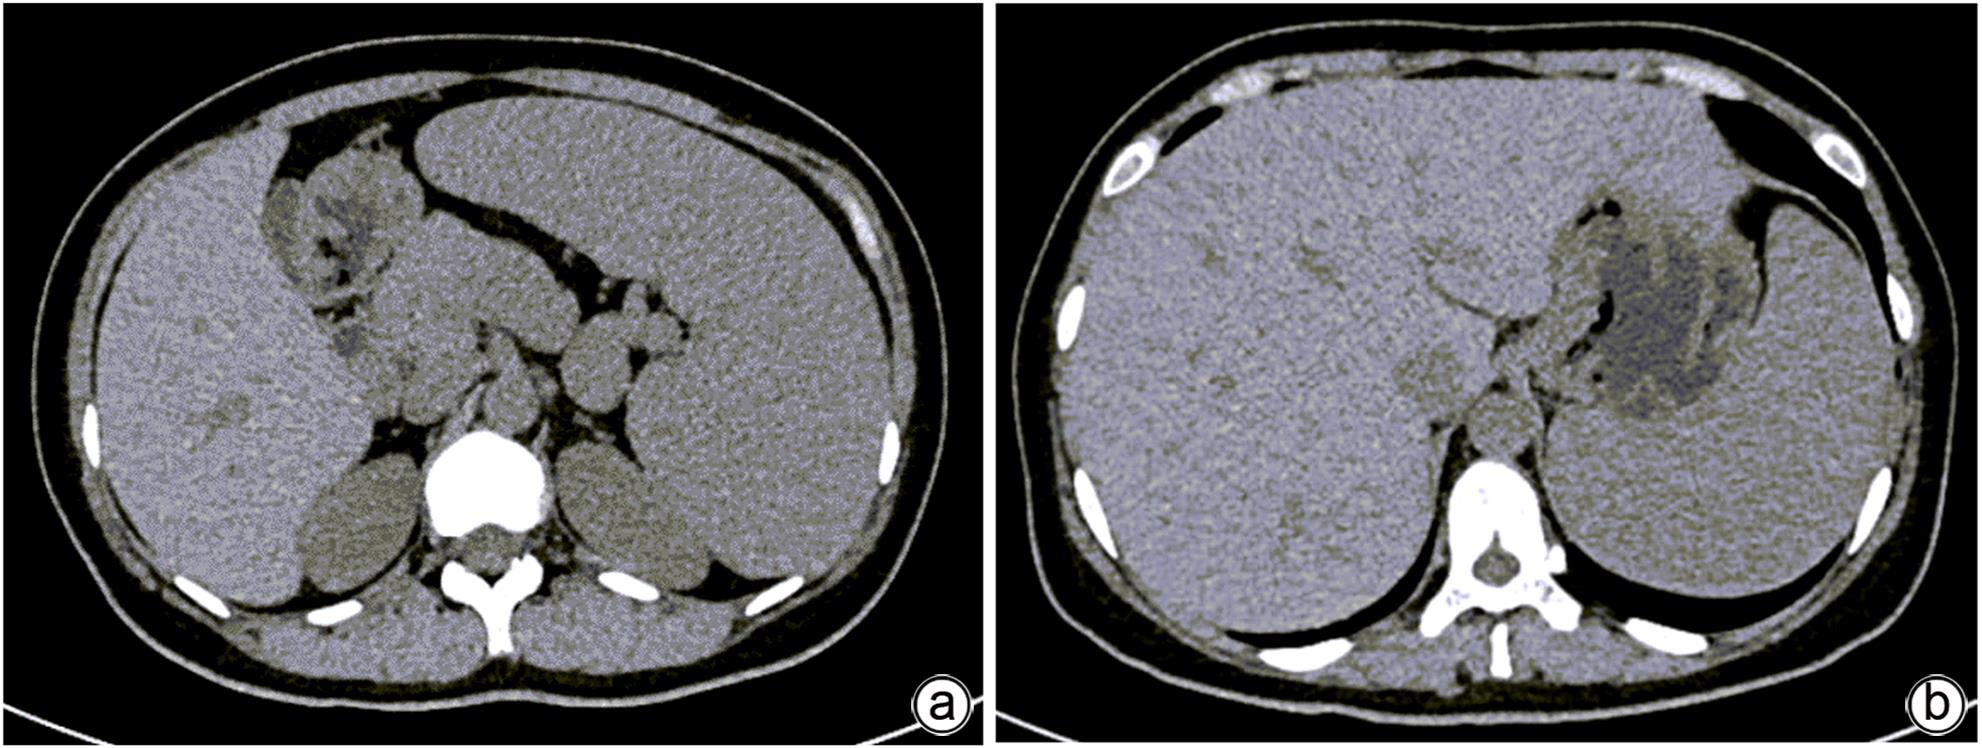

胰腺内副脾误诊2例报告

摘要(1364) HTML (331) PDF (1188KB)(157)

摘要:

副脾是指正常脾脏以外存在的,与主脾结构相似,有一定功能的脾脏组织,其中完全被胰腺包裹的胰腺内副脾(IPAS)发生率仅为2%,因其临床症状不典型,影像学特征与胰腺神经内分泌肿瘤、胰腺实性假乳头状瘤以及其他胰腺占位性病变较为相似,临床上容易误诊。本文报道了2例分别被误诊为胰腺神经内分泌肿瘤和胰腺实性假乳头状瘤的IPAS患者,并分析误诊原因,总结诊疗经验,以期提升临床对IPAS明确鉴别诊断的认识。